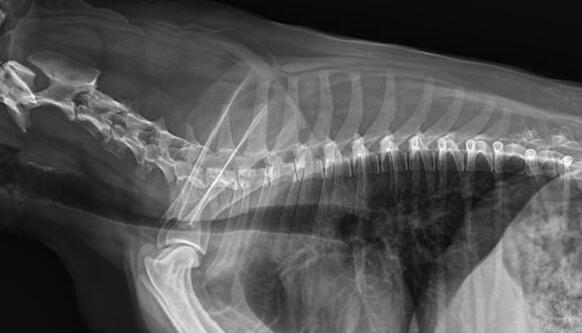

利用寵物dr拍攝圖像效果圖

1、DR的DQE檢測效率可達(dá)74%,而傳統(tǒng)普通膠片組合X線照片DQE為30%。

2、寵物DR成像速度快,采集時間10ms以下,成像時間僅為3秒,對于受傷的寵物來說,檢查越快速,越能早點幫助其治療,降低痛疼。對于寵物主人而言,也是一種心理安慰。

3、數(shù)字圖像可進(jìn)行后處理。圖像后處理是數(shù)字圖像的很大特點。只后要保留原始數(shù)據(jù),就可以根據(jù)診斷需要,并通過軟件功能,有針對性的對圖像進(jìn)行處理,以提高診斷率。

4、獸用dr所具備的輻射劑量較低,相比傳統(tǒng)的ct而言,對于寵物和醫(yī)生而言,都是一種保護(hù)。

5、有效解決了圖像的存檔管理與傳輸,采用光盤刻錄形式保存圖像資料,隨時能為受檢者提供照片打印服務(wù),這樣大大提高了工作效率。對于接診量比較大的寵物醫(yī)院來說,這個具備大的優(yōu)勢。